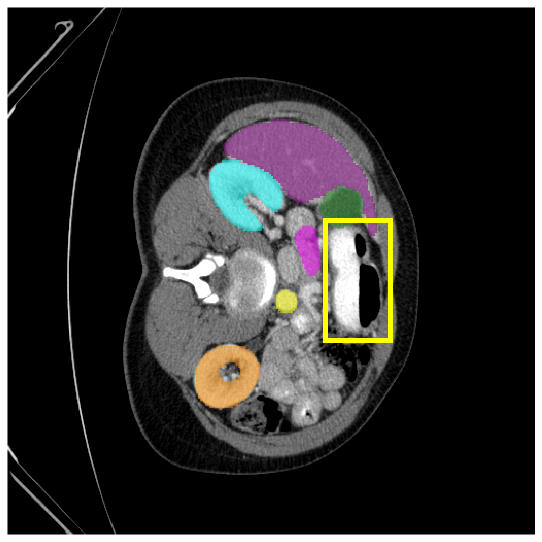

4.3.2 Visual Comparisons

Visualization of our method on the Synapse and ACDC datasets is shown in Fig. 3(a) and Fig. 3(b). For the Synapse dataset illustrated in Fig. 3(a), FCT failed to accurately segment SM and GB, while MERIT achieved precise segmentation of SM but struggled with GB. In contrast, our method achieved accurate segmentation of both SM and GB. Regarding the ACDC dataset shown in Fig. 3(b), while previous methods achieve comparable segmentation of the Myo and LV to the GT, they exhibit noticeable errors on the RV, including invasion into adjacent organs and misrecognition. On the other hand, our method accurately segments across all three structures Myo, LV, and RV, performing as precisely as the GT. We demonstrate the superiority of our method quantitatively and qualitatively.